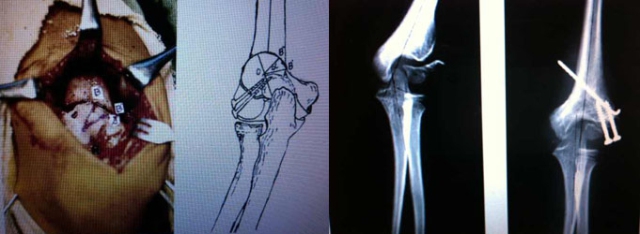

老师:手术目的包括“促进不愈合处愈合+肘外翻畸形矫正”,我会做骨折处的原位加压融合+低位肱骨髁上截骨。一个很重要的原则就是不要做切开复位,不要为了试图做切开复位而过度显露剥离不愈合处,否则可能会严重影响骨块的血运,因为肱骨外髁骨块血供主要来自于后方。

老师:文献核心是对移位不大的外髁骨折不愈合行原位加压以促进愈合,同时做内侧“闭合楔形”截骨纠正肘外翻。肘外翻畸形主要于冠状面,侧方入路就能很好显露,术中用克氏针定位指示截骨方向与水平,似乎没有必要用暴露和损伤相对较大的后侧入路,后方入路发生术后肘关节功能障碍的风险相对较高。因此,我还是习惯采用侧方入路。另外,对于肘内翻畸形的矫正有很多种术式,有研究发现,术式越复杂,术后并发症的风险越高。

学生:做髁上截骨矫形,您会怎么固定?Slongo谈到利用单臂外固定架固定,可以吗?

老师:对于小年龄儿童我会用克氏针固定,青少年可以采用钢板固定。Slongo利用单臂外架行创伤后肘内翻截骨矫形的固定,对三维畸形(冠状面内翻、矢状面前倾丢失、水平面内旋)的纠正可能更有优势。外髁骨折后肘外翻更多是单平面畸形。

对肘内翻等肘关节成角畸形进行矫正时选择合适的截骨水平及截骨方向,术中辅以克氏针C臂定位,可以达到很好的矫形效果。我们的系列病例中,部分矫形不满意,很多与截骨水平不当有关。